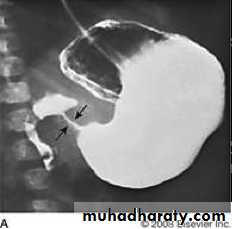

Found in the lower end of esophagus , almost invariably associated with a hiatus hernia and gastro-esophageal reflux. Peptic strictures are characteristically short and have smooth outlines with tapering ends. Ulcer may be seen nearby.

Peptic stricture